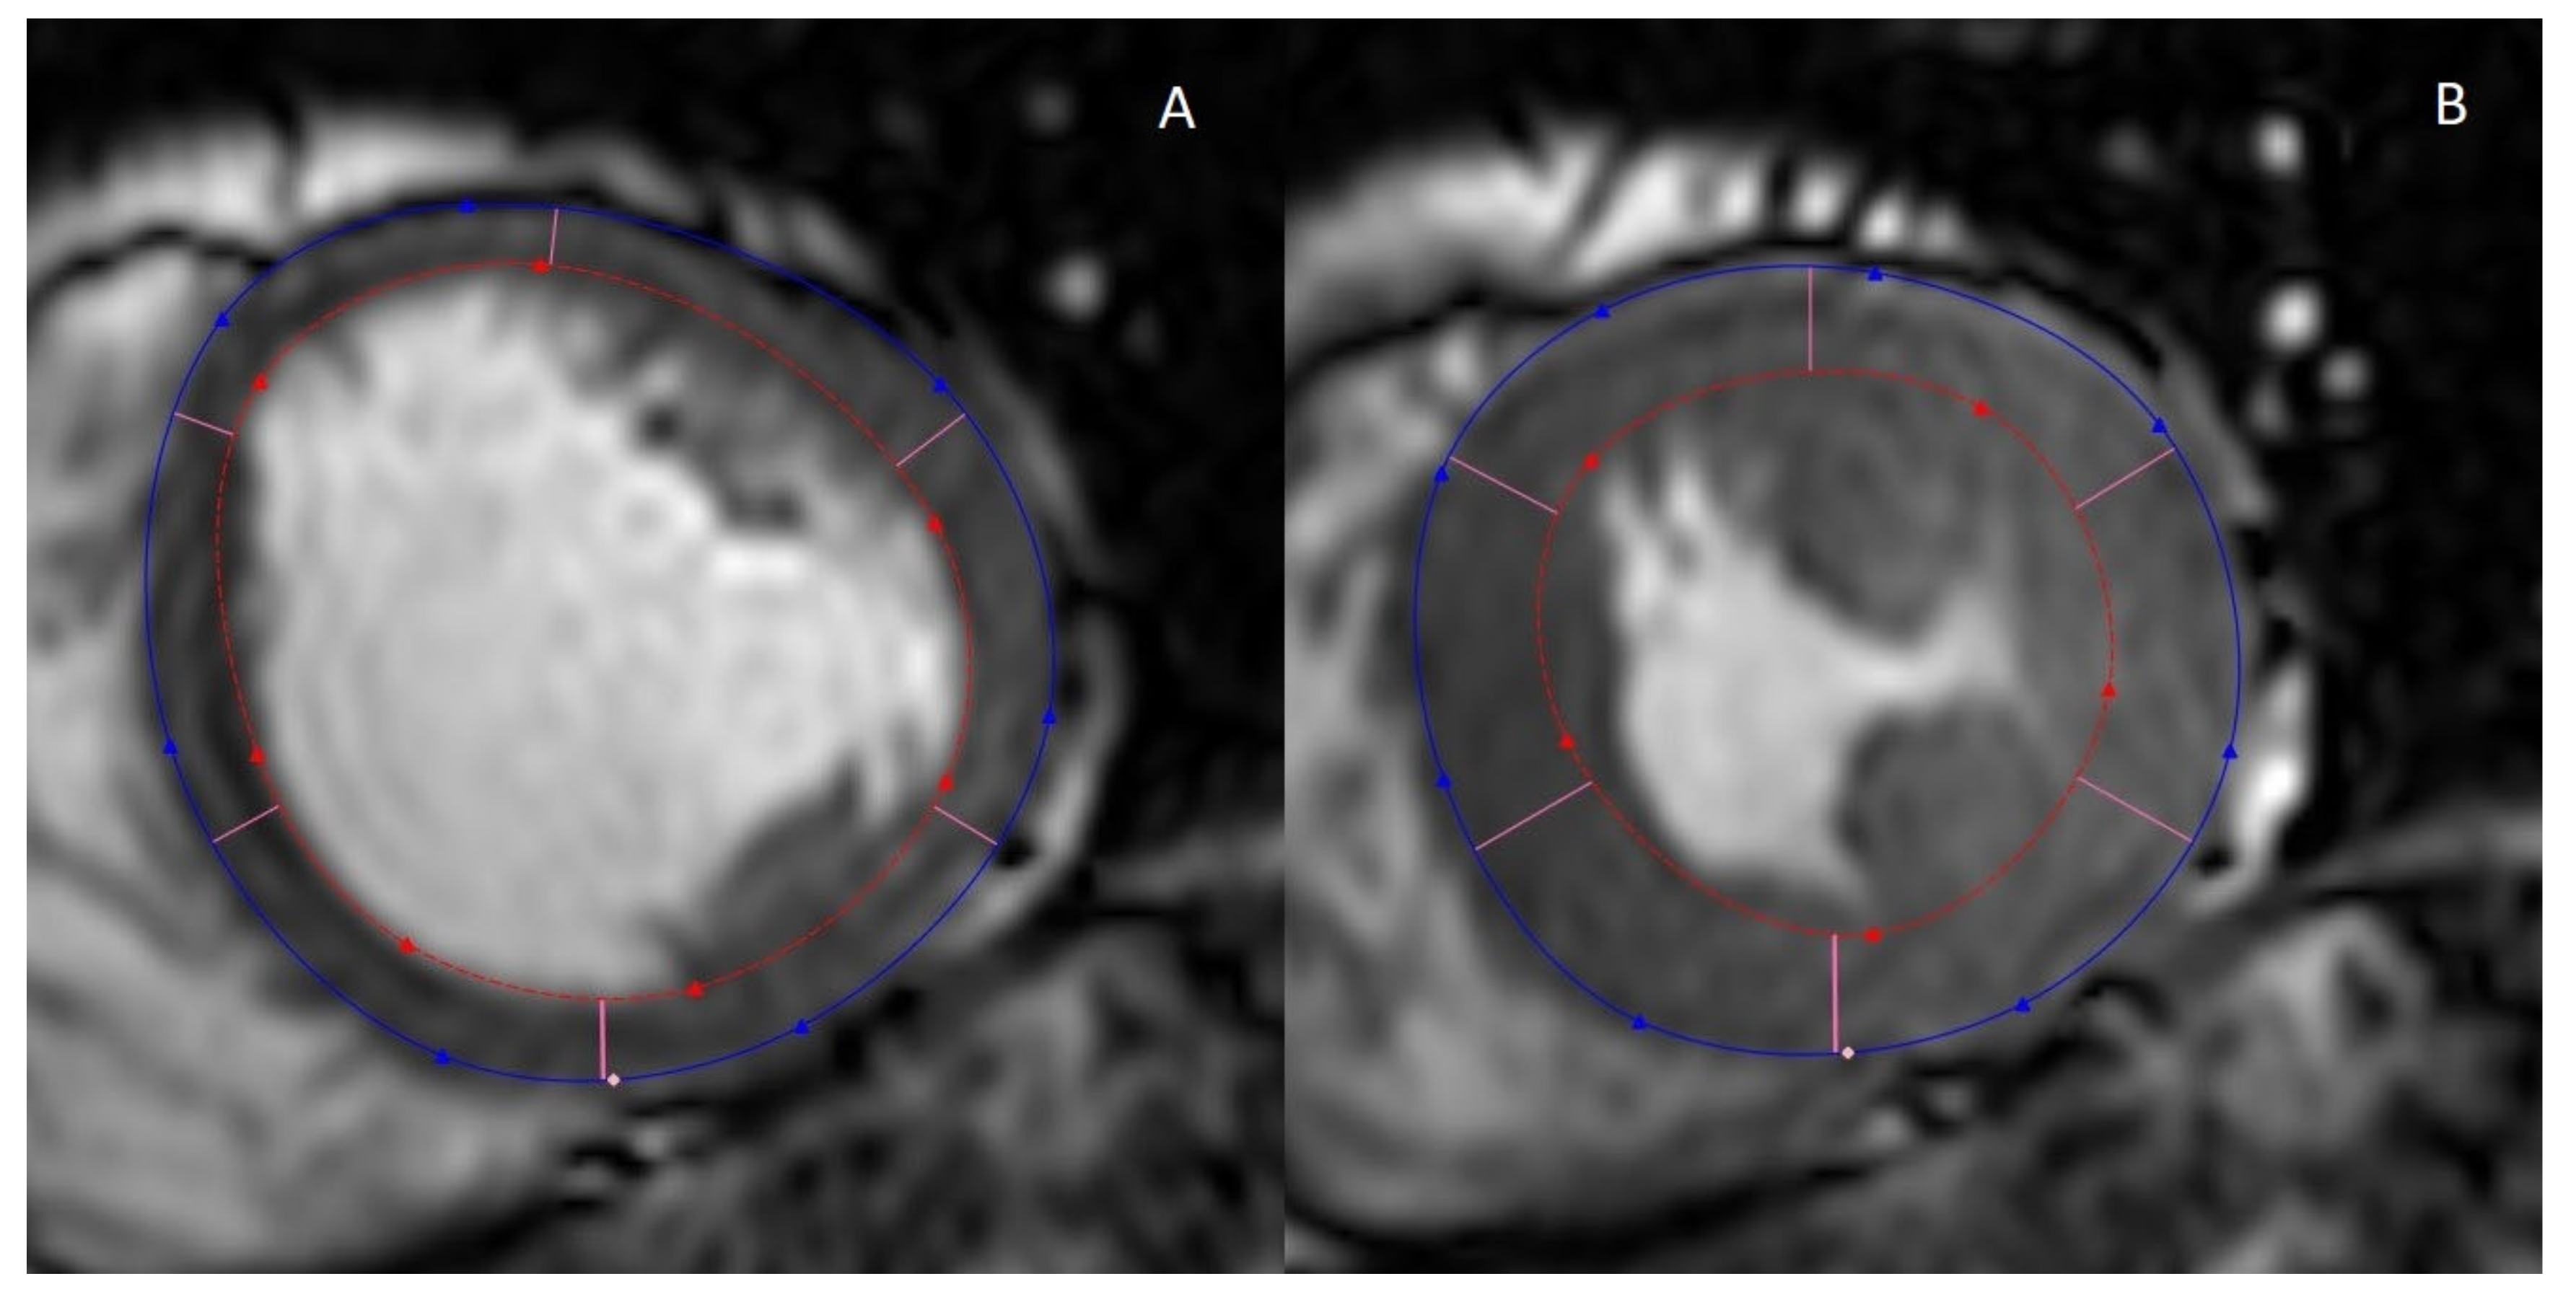

2.1. Cine MRI